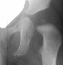

Four months later, the spica cast was removed and an Atlanta brace was applied. X-rays showed avascular necrosis at ten months of age . At two years of age, the ossification of the left nucleus was still delayed. The leg lengths were equal and the range of motion of the hip was full.

The progression of the hip is documented by x-rays taken at 1 year of age, 2 years of age, 3 years of

age, 5 years of age, 7 years of age, then at ten years of age, early closure of the lateral portion of proximal growth plate observed. Coxa valga was also observed.